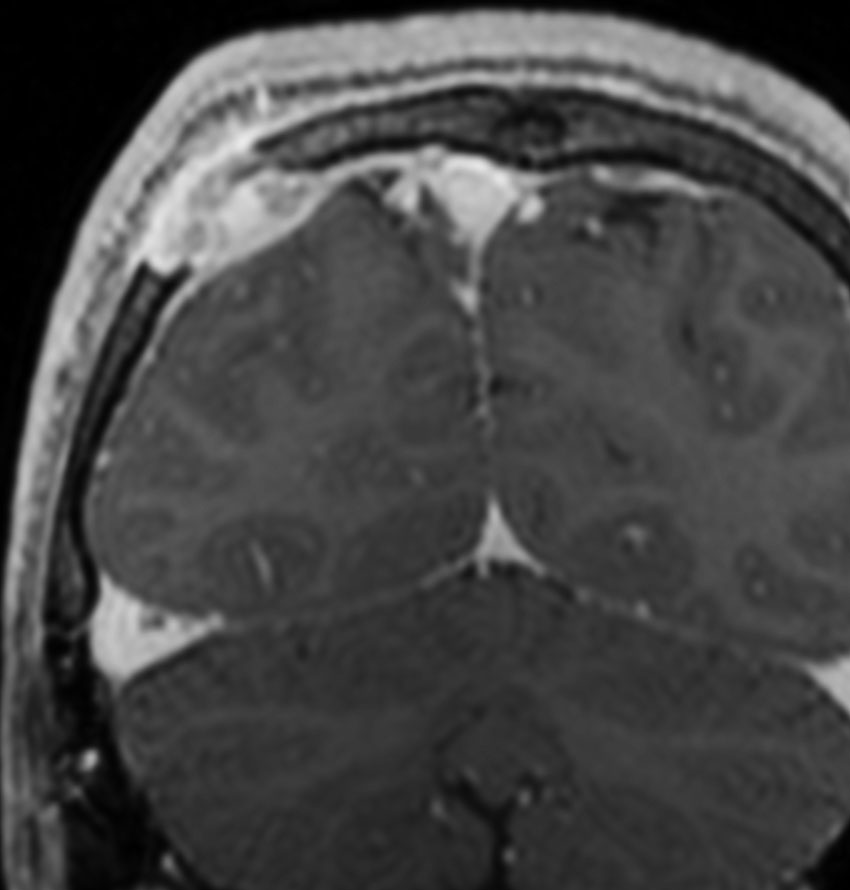

ND-LCH (neurodegenerative LCH) ガドリニウム増強されないタイプ

- 脳のLCHですが,広範囲な病変で,ガドリニウムで白い造影像がでません

- 脳炎のような臨床像です

- T2強調画像の不規則な高信号領域が,両側の小脳白質,大脳基底核,橋,大脳深部白質に生じます

- LCHを有する子どもの20%くらいに画像上の脳病変が生じますが,その内の症候性のものを言います

- 変性性神経疾患のような多発性脳病変と症状を出すものです

- 症状は急激に悪くなることがあります

- 小脳失調,振戦,構語障害,嚥下障害,人格変化,学習障害,知能障害,行動異常,認知障害,精神発達遅滞などを生じます

- 病変が広いと様々な神経精神症状を残してしまいます

- 脳のLCHの代表的な症状が尿崩症なのですが,尿崩症が判明してからND-LCHの症状が出ることが多いです

- 水頭症を合併することがあります